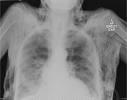

অনুগ্রহ করে অপেক্ষা করুন। ছবি আটো ইন্সার্ট হবে।